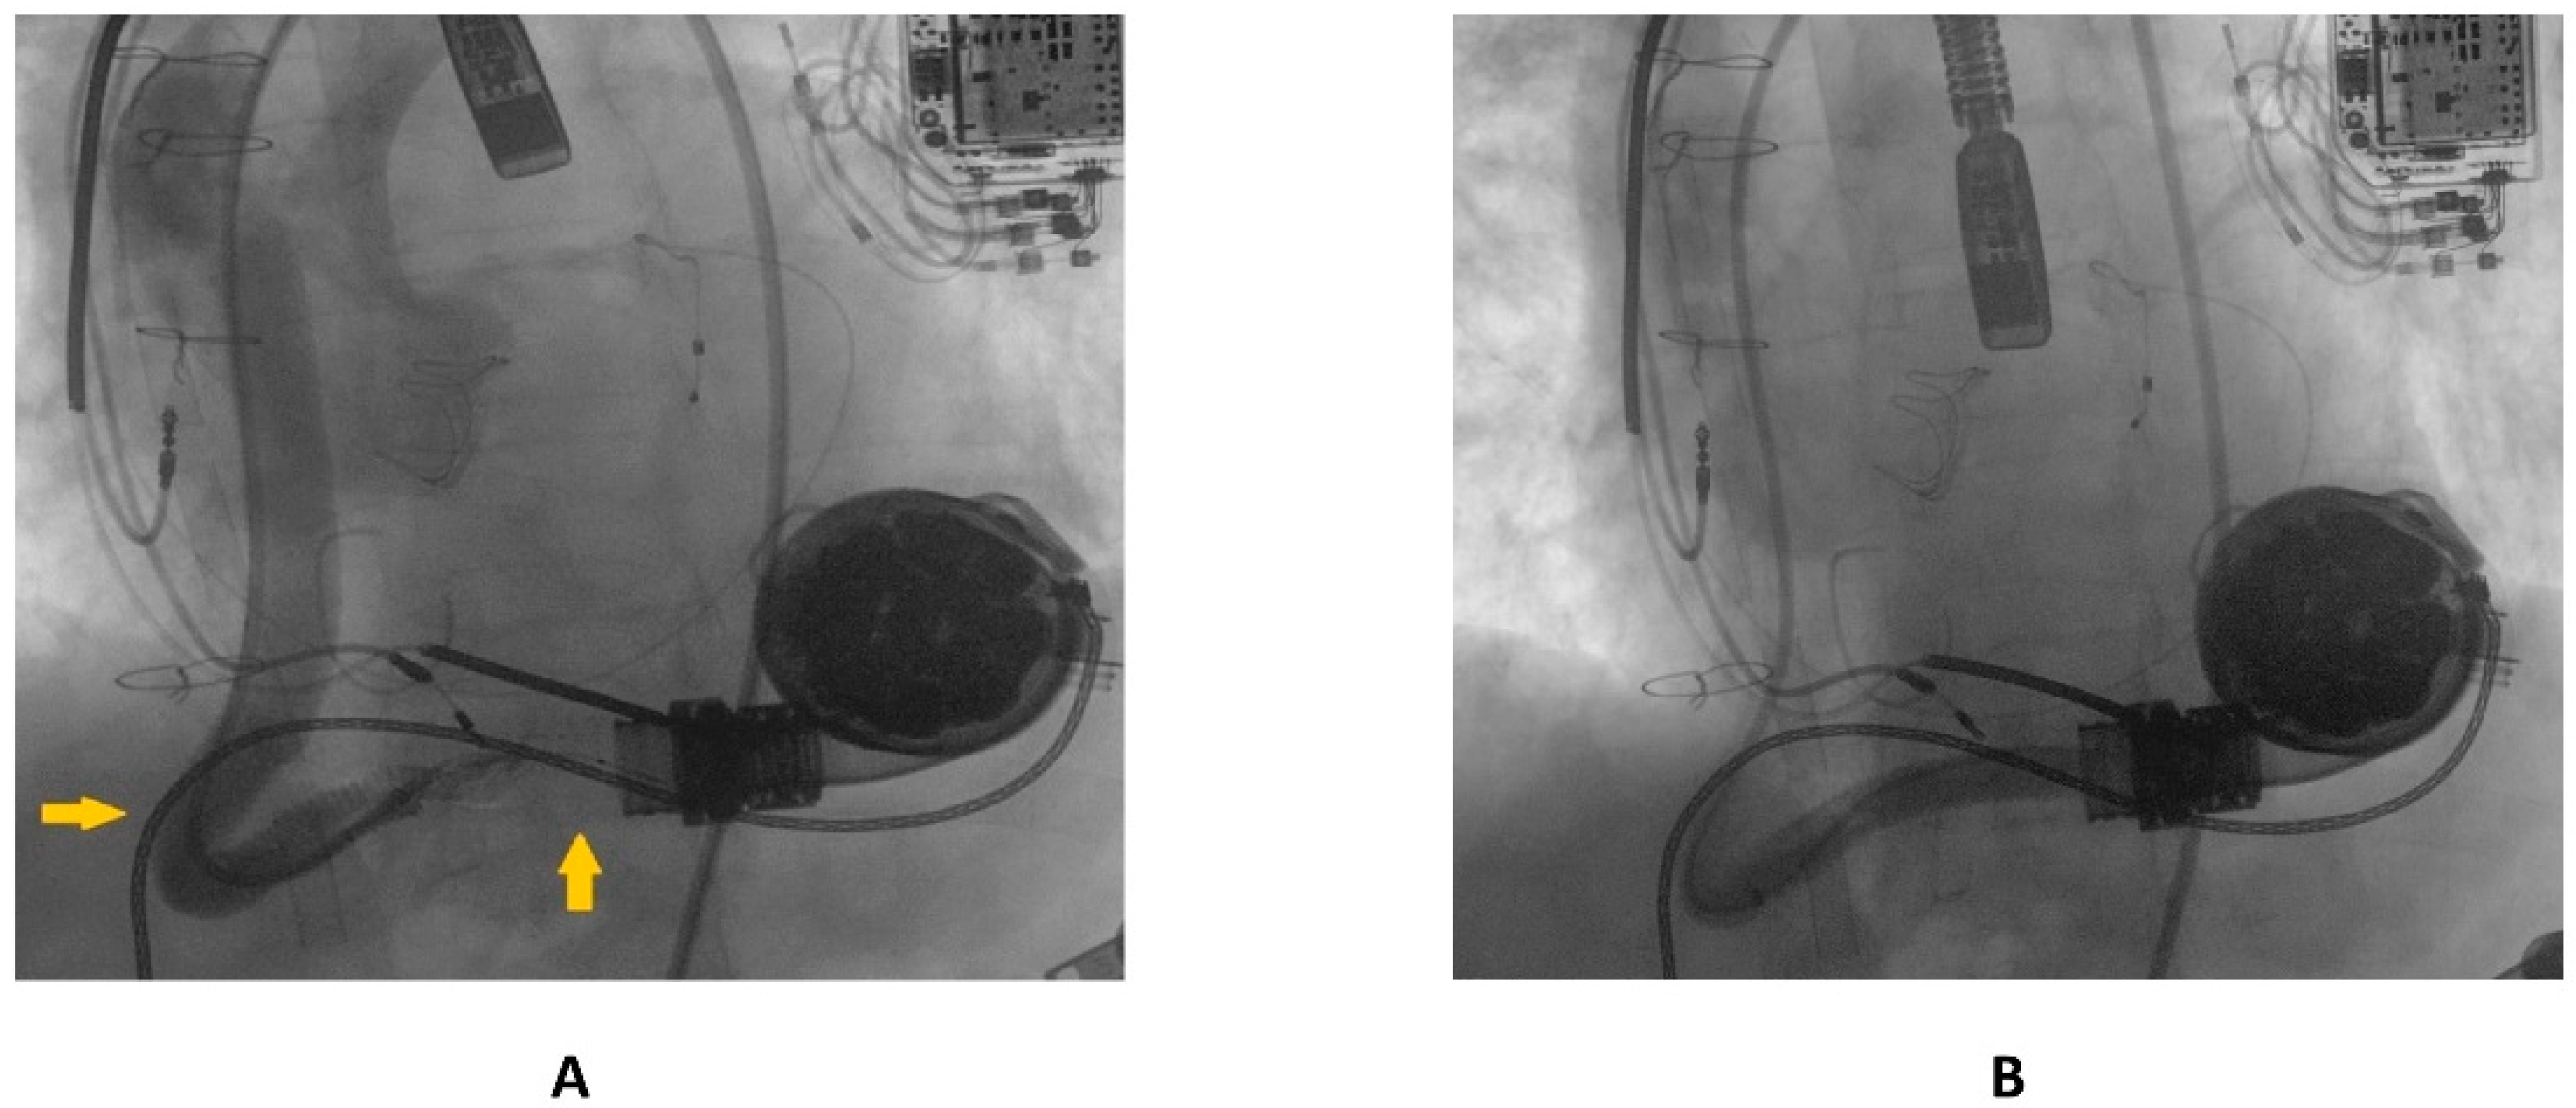

Following this first LVAD intervention, a dual antithrombotic regimen with aspirin and a vitamin K antagonist (VKA) was administered. However, antiplatelet therapy was suspended few months after due to a major neurological bleeding. At admission, the patient showed unstable clinical conditions (systemic blood pressure of 90/60 mmHg, a heart rate of 130 beats per minute, a respiratory rate of 20 breaths per minute, arterial oxygen saturation of 85%). Laboratory markers showed elevated serum lactate and impaired renal function, without signs of ongoing hemolysis. Due to the impeding cardiogenic shock, the patient was admitted to intensive care unit (ICU). Echocardiographic evaluation confirmed the presence of severe LV dysfunction (ejection fraction < 25%) and dilation. Moreover, severe right ventricular (RV) dysfunction (TAPSE < 15 mm) was found. LVAD logged several low-flow alarms (1.5 L/min, 8000 rpm), suggesting that a major device failure could be the trigger of this condition. Considering the unstable clinical setting and the past medical history of OGO [8], computed tomography (CT) was deferred and the patient was directly transferred to the catheterization laboratory to perform an urgent invasive diagnostic assessment. The procedure was performed under general anesthesia and with continuous transesophageal echocardiography monitoring. In order to avoid possible circulatory collapse during the procedure, both the arterial and venous femoral accesses were surgically obtained with the purpose of rapidly deploying veno-arterial extracorporeal membrane oxygenation (ECMO) assistance, if necessary. Via the right femoral artery, a first attempt at performing angiography using a diagnostic pig-tail catheter failed. Considered the presence of a known kinking site [8], an 8F 110 cm-long sheet (Flexor®Ansel Guiding Sheath, Cook Medical, Bloomington, IN, USA) was conducted through the distal anastomosis of the outflow graft to provide further support. Following this, a 130 cm-long supporting catheter (TrailBlazer™, Medtronic) over standard 0.035″ × 260 cm hydrophilic guidewire was advanced beyond the kinking and a diagnostic angiography was performed. As showed in Figure 2, a discrete filling defect located at the kinking site was found, suggesting recurrent thrombosis.

Figure 2.

Diagnostic angiography showing recurrent outflow graft obstruction (yellow arrow).